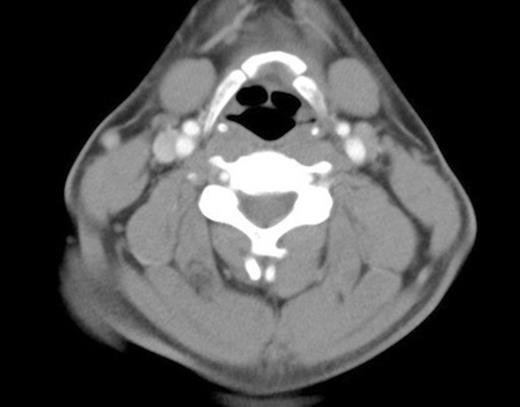

The mechanism of injury and examination findings raised a clinical suspicion of a severe traumatic insult, and he was admitted on the ENT ward to undergo an urgent CT scan of the neck. This demonstrated dislocation of the symphysis between the left medial greater cornu and left body of the hyoid (figure 1).

Dislocation of the symphysis between the left greater cornu and the body of the hyoid bone